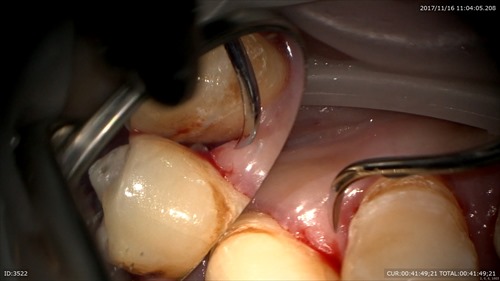

岩石のような歯石を歯と歯茎の間に発見

マイクロスクープでくっきり見えます。当院では衛生士が歯茎よりも上のデブライドメントを私が歯茎よりも下の治療を行いチームで歯周病治療を行います。患者さまも今までは衛生士さんのみに歯石をとって頂いていたと言っていました。この歯周病のデブライドメントはそんなに簡単な仕事ではありません。歯周組織の解剖とセメント質の厚み、年齢、超音波での1回あたり削れる量。手用スケーラーの一回で削れる量。などありとあらゆる条件を計算し取り組む必要があり、やりすぎると象牙質が削れたりそのせいでしみます。だから私が難しい所はすべて歯周病専門の私が担当しています。

丁寧に。無痛下で。この患者さまは7回目のデブライドメント。

術前(左)術後(右) 綺麗な根面になりました。